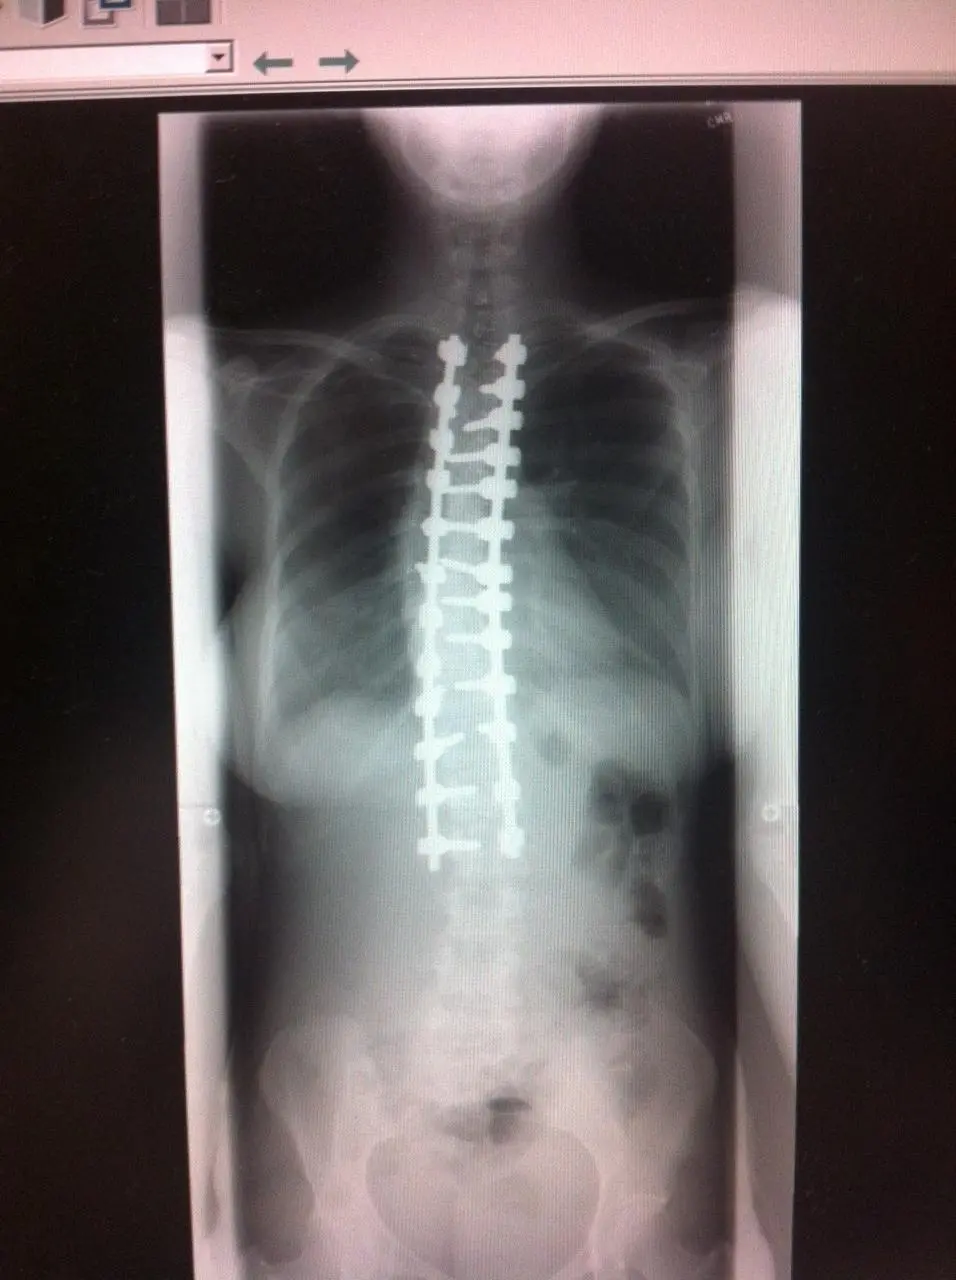

ทว่าสำหรับกรณีของหญิงสาวรายนี้อาการของโรคค่อนข้างแย่มากๆ เนื่องจากกระดูกสันหลังของเธอนั้นมีความคดของกระดูกสันหลังประมาณ 90 องศา และเธอจำเป็นต้องได้รับการผ่าตัดแก้ไขโดยแพทย์ผู้เชี่ยวชาญ และหลังจากที่แพทย์ได้ทำการผ่าตัดได้สำเร็จ ก็สามารถลดความโค้งของกระดูกสันหลังลดลงกว่า 20 องศา

สำหรับช่วงเวลาการพักฟื้นอาจใช้เวลาค่อนข้างนานพอสมควร เพราะผลจากการผ่าตัดอาจทำให้เกิดอาการปวดหลัง รวมไปถึงภาวะแทรกซ้อนอื่น ๆ แต่อย่างไรก็ตาม การผ่าตัดประเภทนี้ไม่เพียงแต่ดีต่อสุขภาพของผู้ป่วยในระยะยาวเท่านั้น แต่ยังช่วยยืดกระดูกสันหลังของผู้ป่วย ซึ่งจะทำให้พวกเขาดูสูงขึ้นอีกด้วย